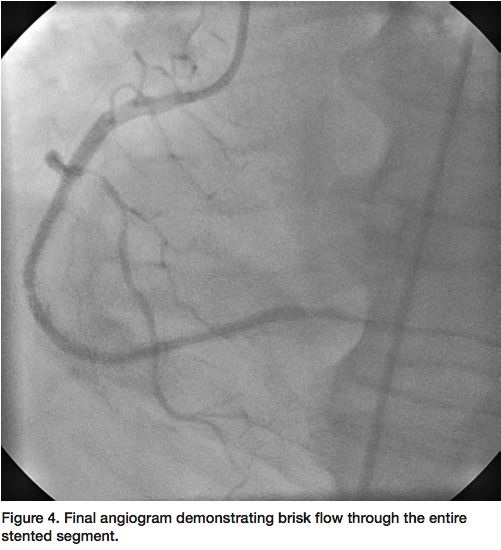

A 6 French JR4 guide was used to engage the RCA. A Prowater wire (Asahi Intecc) was initially advanced but unable to cross the lesion. A PT Graphix wire (Boston Scientific) was then advanced with the use of an Apex 1.5 mm over-the-wire balloon (Boston Scientific) for support to cross the occluded segment into the distal RCA. Due to the degree of thrombus burden, laser atherectomy was performed (Figure 2) using a 0.9 mm ELCA catheter (Spectranetics) with no improvement in flow. Intravascular ultrasound (IVUS) of the entire stented

segment revealed an under-expanded stent with a reference vessel size of 4 mm. An NC Sprinter 4.0 mm balloon (Medtronic) was used to further dilate the stented segment, but with no improvement in flow. A ClearWay 1.0 x 10 mm perfusion balloon (Atrium) was then used to deliver intracoronary nitroglycerin, adenosine, and eptifibatide (Figure 3), with still no distal flow. Finally, the ClearWay balloon was used to deliver intracoronary tPA (2 mg bolus) with significant improvement in flow after 5 minutes of dwell time. Final angiogram revealed brisk TIMI-3 flow through the stented segment with excellent angiographic result (Figure 4).